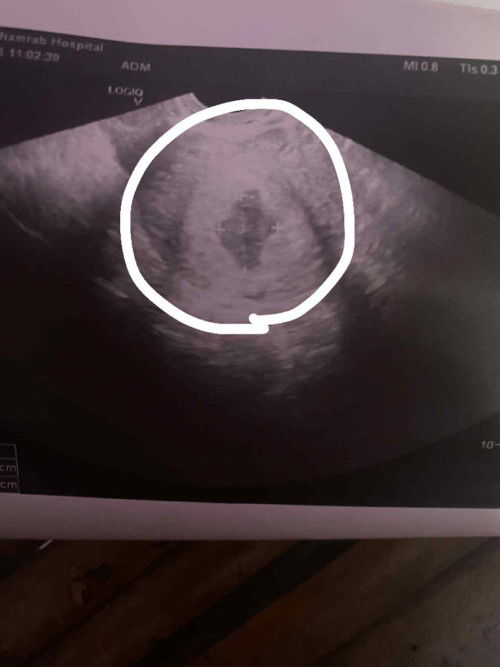

ปจด ขาด3เดือน ปกติเปนคนปจด มาไม่ปกติอยู่แล้ว อยู่ๆลองตรวจฉี่ สรุป ท้องจ้าาา เลยรีบไปฝากครรภ์เพราะอายุครรภ์น่าจะ13วีคแล้วว ไปซาวที่ รพ. งง ไปอีกเพราะ เจอแต่ถุงตั้งครรภ์ หมอบอกน่าจะ เพิ่ง6วีค ต้องไปซาวใหม่อีก 2สัปดาห์ เราจะเจอเด็กไหม หรือเป็นท้องลม